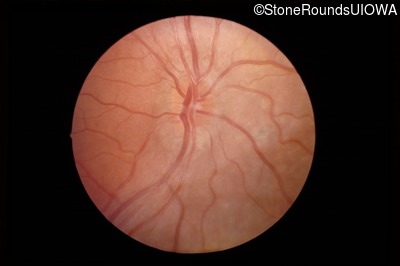

Fundus Photography - Right - 20/40 -2

Exemplar